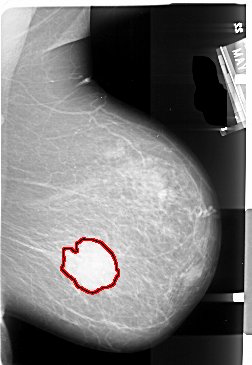

A_1004_1.LEFT_MLO

FILE: A_1004_1.LEFT_MLO.OVERLAY

TOTAL_ABNORMALITIES 1

ABNORMALITY 1

LESION_TYPE MASS SHAPE IRREGULAR MARGINS SPICULATED

ASSESSMENT 5

SUBTLETY 5

PATHOLOGY MALIGNANT

TOTAL_OUTLINES 2

BOUNDARY

CORE